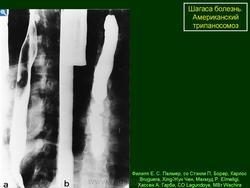

На протяжении второй стадии паразиты концентрируются, в основном, в сердце или мускулатуре пищеварительного тракта. До 30% пациентов страдает от нарушений сердечной деятельности и до 10% – от изменений в органах пищеварения (характерна гипертрофия пищевода или толстой кишки), нервной системе или целом ряде органов. В последующие годы инфекция может приводить к внезапной смерти или сердечной недостаточности, вызываемой прогрессивным разрушением сердечной мышцы.